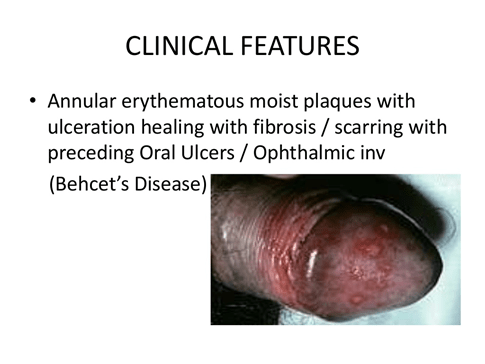

Balanoposthitis:

Balanitis is the term for inflammation of the glans penis. Posthitis is defined as inflammation of the prepuce.

Balanoposthitis is inflammation of both It is fairly common, occurring in 4–11% of uncircumcised boys.

The etiology is unclear and no cause can be identified in many cases, although infection, mechanical trauma, contact irritation, and contact allergy are cited.

Management of balanoposthitis includes improved hygiene with gentle foreskin retraction, sitz baths, and cleaning of the foreskin.Topical ointment and oral antibiotics are indicated for suspected acute bacterial balanoposthitis. Because Group A beta hemolytic streptococcus is a common bacterial cause of balanoposthitis, first-generation cephalosporins or penicillins have been typically recommended.